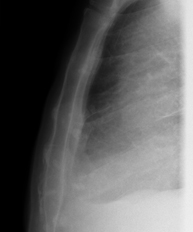

- Tórax

- RX Tórax

Técnica mediante la cual, utilizando rayos X, se obtienen imágenes de la caja torácica (corazón, pulmones, arcos costales, clavículas, etc.) para su estudio. - RX Esternón

- Chest X-ray

A chest X-ray uses a small dose of radiation to obtain a two-dimensional image of the thoracic cavity and its contents (lungs, heart, mediastinum, etc.). It is one of the most commonly performed medical tests.